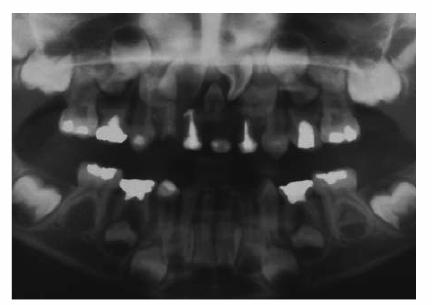

Approach

A male patient, 36 months old.

PROBLEM: He presented with rampant caries involving four maxillary

anterior teeth and caries in the lower arch. The parents hoped that the teeth

could be saved. Initial radiographs were taken (Figures 27-2A

and B

Figure 27-2A and B: Rampant caries involving the anterior teeth and the lower arch.

TREATMENT: Caries were removed, and endodontic treatment was performed.

Aluminum oxide posts were used. A rubber-base impression was made for

laboratory-processed full acrylic crowns (Figure 27-2C

Figure 27-2C: Crowns are seated with an acceptable result.

RESULT: Crowns were seated with an acceptable result. Figures 27-2A and 27-2D show the sharp contrast between

before and after treatment. The child was able to resume his usual activities

without discomfort or fear of future embarrassment.

Figure 27-2D: The radiograph shows the endodontic treatment performed and the restoration of the lower caries.